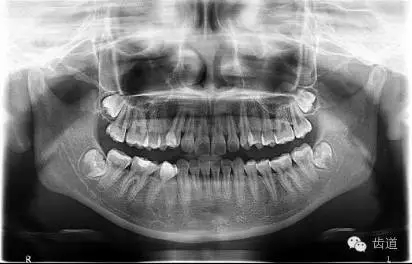

1.術(shù)前全景片

可見37根尖周有明顯透射影像(患者當(dāng)日懷疑第三磨牙阻生問題,初診科室為外科,擬行雙側(cè)阻生齒拔除術(shù),故已向行全景片拍攝)

2. 術(shù)前X片

可見37根管影像清晰,根中上三分之二粗大,根尖三分一分為近遠(yuǎn)中兩根管,形態(tài)均呈弧形,根尖周膜連續(xù)性中斷,根尖周透射影明顯